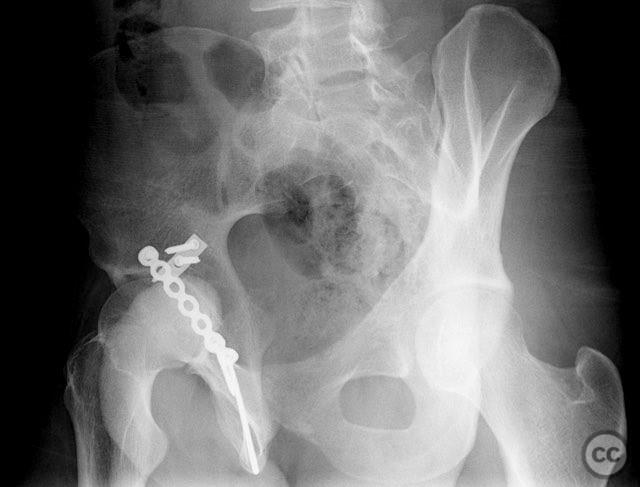

Clinical and radiological findings:  A 20-year-old male collegiate basketball player sustained a displaced right posterior wall (PW) acetabular fracture-dislocation during practice. Initial AP pelvic radiograph demonstrated a reduced femoral head with a displaced posterior wall fragment. Axial CT imaging revealed a large, peripherally located PW fragment with significant displacement, impaction into the abductor muscle mass, and no intra-articular comminution. Obturator oblique radiographs and intraoperative fluoroscopy under anesthesia demonstrated mechanical obstruction to passive abduction at 10–20 degrees due to the relationship between the displaced PW fragment and the greater trochanter.

Intraoperatively, the posterior wall fragment was found firmly embedded within the abductor musculature, necessitating careful disimpaction and minimal periosteal stripping to preserve vascularity. The spring-hook device provided secure capture of the peripheral fragment without involving the labrum. Placement of the reconstruction plate medial to the hook tines provided buttress support to prevent secondary displacement. Fluoroscopic imaging confirmed anatomic reduction and extra-articular screw placement. Postoperative CT demonstrated satisfactory reduction and implant positioning.